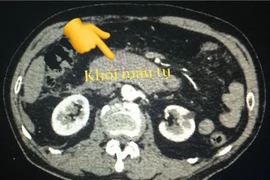

Bệnh nhân nhập viện trong tình trạng trụy mạch, vỡ thận trái, vỡ lách, chảy máu ổ bụng, tình trạng rất nguy kịch, nguy hiểm tính mạng... đã được cứu sống thành công.

(khoahocdoisong.vn) - Các chấn thương vào bụng tùy theo mức độ có thể từ đơn giản đến nghiêm trọng. Những chấn mạnh có thể gây vỡ tạng, tổn thương mạch máu ở ổ bụng, gây chảy máu trong ổ bụng gây sốc mất máu, có thể đe dọa tính mạng nếu không phát hiện và xử trí kịp thời.